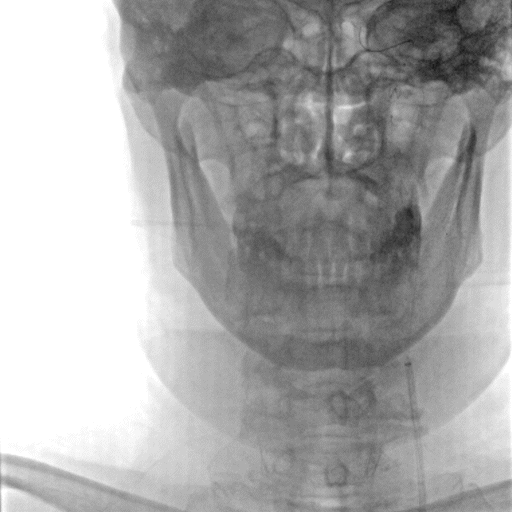

主动脉弓造影见弓上血管走行III型弓,开口处无明显斑块形成。

常规消毒、铺巾后,采用改良Seldinger技术穿刺右桡动脉。造影导丝和Sim2造影导管将7F EasyRadial™输送导管置于椎动脉。

正侧位造影提示右侧椎动脉重度狭窄。